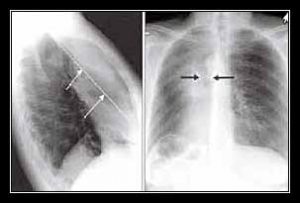

. Tâm nhĩ trái lớn (hẹp lỗ van hai lá), v.v…